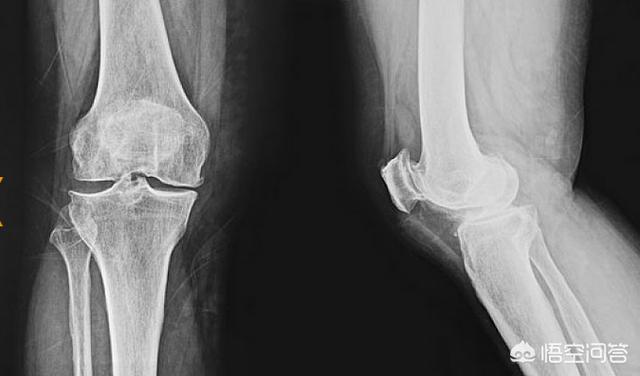

1.50歳以上の高齢者は、関節機能の退化による膝軟骨のすり減りに悩まされ、膝内側の痛みを誘発する。高齢者の体力低下により、膝蓋周囲組織の脆さが増し、両足交互に歩くことを繰り返す過程で、膝の内側壁が繰り返し引っ張られ、限界以上に引っ張られた後、わずかな裂傷が生じ、その周囲に水腫が生じます。長年の粉砕の後、関節面軟骨と半月板軟骨の損傷は尽き、基本的に大腿骨内側顆と脛骨内側顆の骨の間に粉砕を形成する。

2.若い人の場合、膝の内側の痛みはたいてい膝の靭帯の損傷が原因です。若い人は関節面の軟骨が非常に厚く、半月板軟骨がクッションになっているため、大きな損傷はありません。臨床的には、膝の内側に痛みと腫れが現れます。痛みがあるにもかかわらず、X線検査では骨の変化は認められません。

3、一種の膝の内側の痛みは、膝半月板の損傷によって引き起こされることもあります。膝半月板は軟骨の一種で、膝関節の太もも部分とふくらはぎ部分の真ん中にあり、膝関節の力の伝導に重要な役割を果たしています。膝の半月板が損傷すると、体の力が膝関節に均等に伝わらなくなり、変形性膝関節症が早期に発生しやすくなり、膝関節痛が起こります。膝半月板損傷は2つのケースに分けられます。1つ目は外傷性損傷です。スポーツでは膝半月板損傷が起こりやすい。二つ目は、変性損傷です。年をとるにつれて半月板は変性し、断裂したり損傷したりします。半月板損傷は膝の靭帯損傷と同時に起こることが多い。

膝半月板損傷の2つの最も一般的な症状は、損傷部位の痛みと腫れです。膝の内側に痛みと腫れがある場合は、膝の内側半月板損傷の可能性が高い。内側半月板損傷後は、膝関節のポキポキという音や、膝が動かなくなる感じがしばしば見られます。